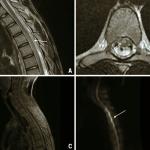

Ischémie médullaire

Un jeune homme de 17 ans, sans antécédent personnel ni familial, est admis au service des urgences pour un déficit...